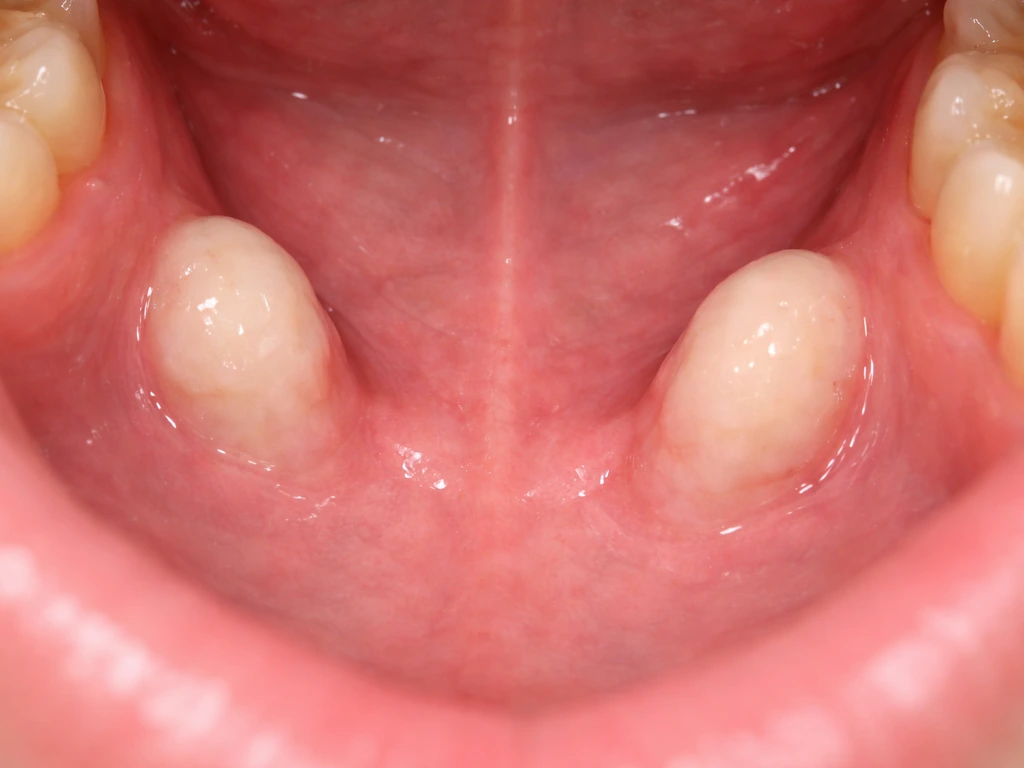

Mandibular tori (singular: torus mandibularis) are benign bony outgrowths that form on the lingual side of the lower jaw, the surface that faces your tongue. Clinically they are classified as exostoses, meaning localized outgrowths of cortical bone that are continuous with the normal jawbone underneath. They are hard, fixed, covered by a thin layer of oral mucosa, and completely noncancerous.

Distinguishing tori from other jaw lesions matters clinically too. Osteomas, ossifying fibromas, and osteochondromas can all look similar on a quick exam but behave differently. What separates a torus from these is that it shows clear continuity with the cortical bone on imaging, has a predictable location, and stays benign. That is why a dentist who is unsure will order a CT or CBCT rather than just watching: the imaging confirms the diagnosis and rules out anything more concerning.